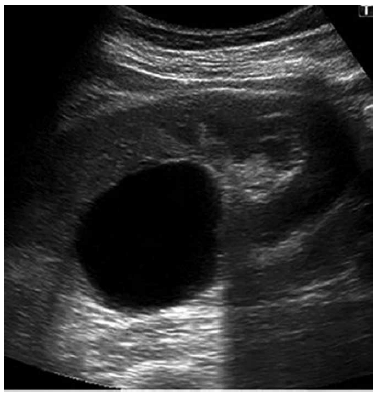

Conforme a onda de ultrassom se propaga no corpo do paciente, ela sofre mudanças físicas.

Assinale a alternativa que melhor descreve essas mudanças.